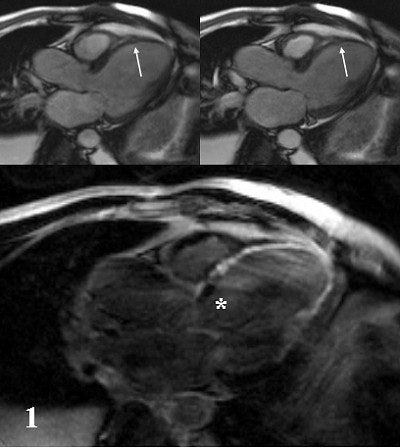

| The same patient. Echocardiography in corresponding apical LVOT view. Top, diastolic (left) and systolic (right) image in rest study. Bottom, diastolic (left) and systolic (right) image during infusion of 10 µg/kg/min. of dobutamine (Stress). Arrows show akinesis in rest and under stress indicating scar corresponding to MRI. Asterisk shows slight improvement of basal segment under stress, indicating viable but ischemic myocardium as suggested on MRI. Images courtesy of Dr. Peter Hunold. |